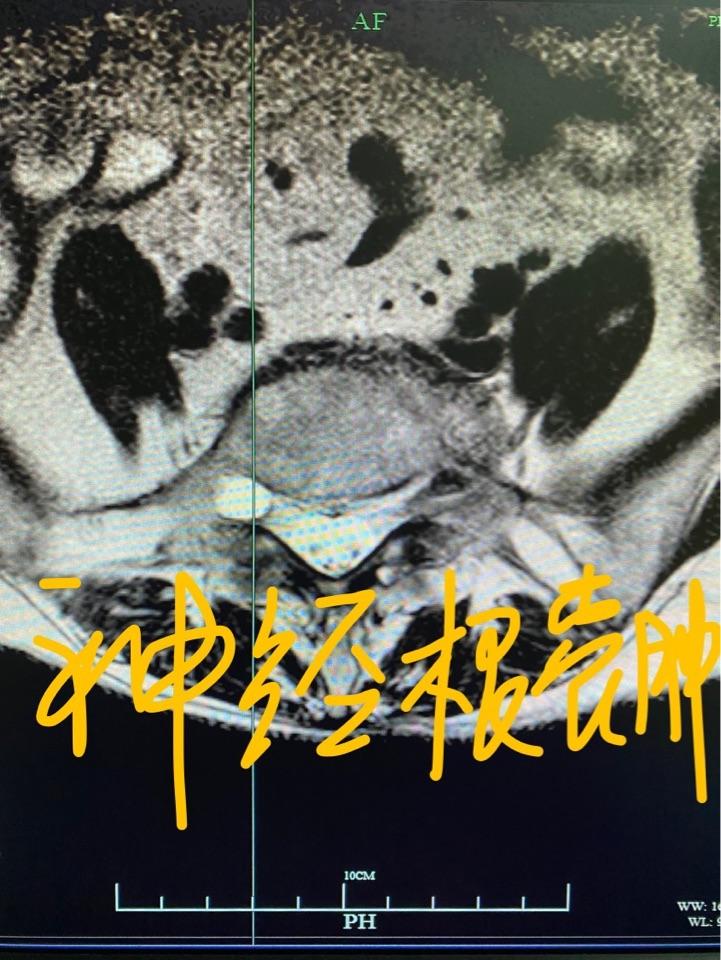

磁共振轴位片发现的腰5右侧神经根上的囊肿